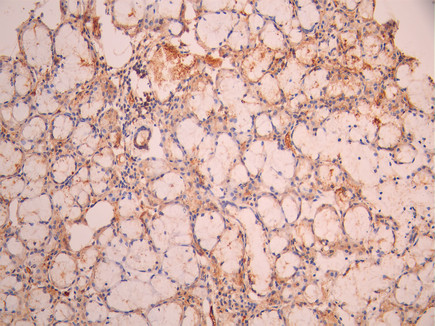

IHC image of CSB-RA005166MA1HU diluted at 1:50 and staining in paraffin-embedded human small intestine tissue performed on a Leica BondTM system. After dewaxing and hydration, antigen retrieval was mediated by high pressure in a citrate buffer (pH 6.0). Section was blocked with 10% normal goat serum 30min at RT. Then primary antibody (1% BSA) was incubated at 4°C overnight. The primary is detected by a Anti-Human lgG, Fcy Fragment Specific labeled by HRP and visualized using 0.05% DAB.

IHC image of CSB-RA005166MA1HU diluted at 1:50 and staining in paraffin-embedded human salivary gland tissue performed on a Leica BondTM system. After dewaxing and hydration, antigen retrieval was mediated by high pressure in a citrate buffer (pH 6.0). Section was blocked with 10% normal goat serum 30min at RT. Then primary antibody (1% BSA) was incubated at 4°C overnight. The primary is detected by a Anti-Human lgG, Fcy Fragment Specific labeled by HRP and visualized using 0.05% DAB.